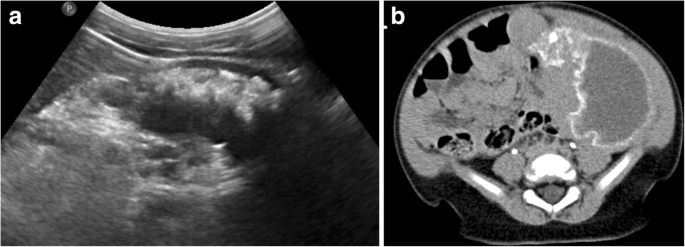

Similar to the previously described hepatic lesions thought to represent focal Gaucher cell buildup, patients with Gaucher disease are often noted to have hyperechoic splenic lesions on ultrasound in one-fifth to one-third of cases [43]. These lesions tend to be low in attenuation with occasional peripheral calcification on CT [55]. On MRI, Gaucher-related splenic nodules usually demonstrate low T1-weighted and high T2-weighted signal intensity, although focal areas of necrosis are also encountered which can be hypointense on T1-weighted imaging [32, 55]. Early MRI studies demonstrated that numbers of splenic nodules correlated with spleen size; these investigators posited that these lesions often represent areas of infarction in the setting of splenic infiltration [56]. These splenic nodules appear to be more common in adults, likely reflecting longstanding infiltration needed to result in ischemia [51]. Similarly, subcapsular splenic infarcts were commonly noted as well prior to introduction of effective ERT [51]. In especially severe cases, splenic necrosis may occur with replacement with fluid attenuation material and peripheral calcification (Fig. 5).

Splenic necrosis in pediatric Gaucher disease. Transverse grayscale abdominal ultrasound (a) of a 2-year-old male Gaucher disease patient with marked splenomegaly shows replacement of normal splenic parenchyma with fluid and hyperechoic regions corresponding to dystrophic calcification. Contrast-enhanced abdominal CT (b) of this patient demonstrates enlarged spleen replaced with liquefying necrosis and peripheral dystrophic calcifications